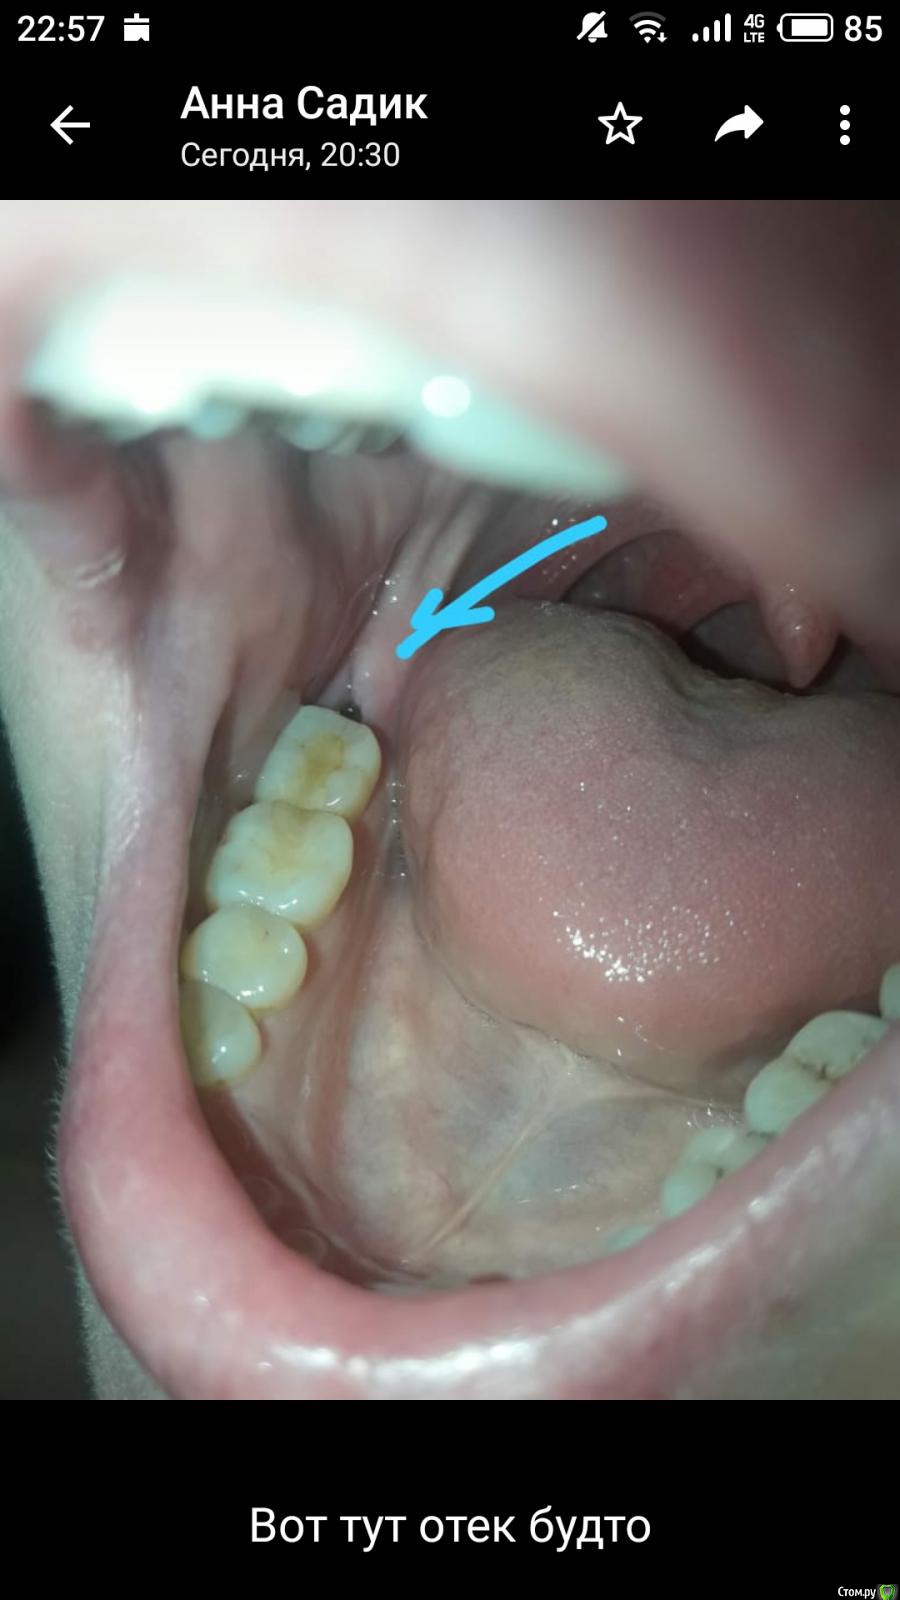

enka Опубликовано 9 февраля, 2020 Автор Поделиться Опубликовано 9 февраля, 2020 Уважаемые, Доктора, доброй ночи. Зуб удалили 8 дней назад. Первые трое суток болел сильно, сейчас болит слабее и пульсирует . Когда же это пройдет? Полоскает мирамистин или сода с солью. Языком чувствует припухлость. Спасибо всем Ссылка на комментарий